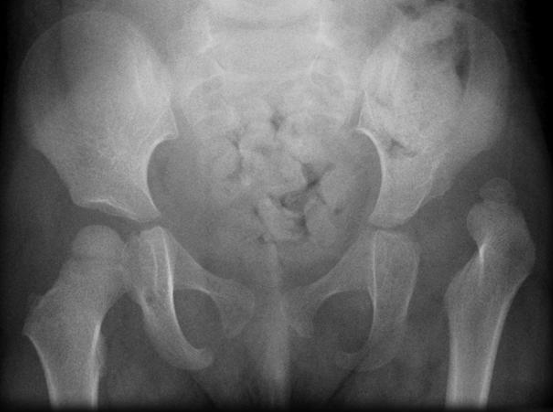

Salter osteotomy |

Dega osteotomy |

Chiari osteotomy |